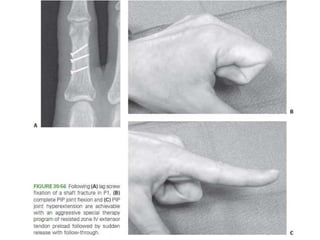

• #83 Figure 30-50 In long oblique fractures of the shaft with shortening an exact reduction and stability sufficient to withstand early motion can be achieved through lag screw fixation only.